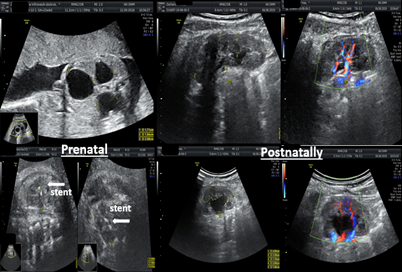

Figure 5,6 shows a case of bilateral nephroamniotic shunting surgery with the "SDE-MED" stent in case of PUV. Stent expulsions were not observed. Shunting surgery of the left fetal kidney was performed at 22 weeks of pregnancy, after 500 ml of amnioinfusion, and the shunting surgery of the right kidney was performed at 24 weeks of pregnancy. During the first procedure of intrauterine shunting, there was pronounced oligohydramnios, and the amniotic fluid index was equal to 4 cm, which required amnioinfusion in the volume of 500 ml. Indications for shunting surgery of the right kidney were grade III hydronephrosis, which did not stop after shunting surgery on the left kidney. Postnatally, the function of both kidneys was preserved. After surgical correction of the PUV disorder, the patient currently has pyelectasia in the left kidney.

Figure 7 shows a case of nephroamniotic shunting for unilateral hydronephrosis of grade III to IV in a fetus at 22 weeks of gestation. The "SDE-MED" stent remained in the left kidney of the fetus for 17 weeks, and 6 days, delivery was performed through the natural birth canal, the stent was removed after the birth of the child in the maternity ward, and postnatal correction of the urinary system defect was not required.